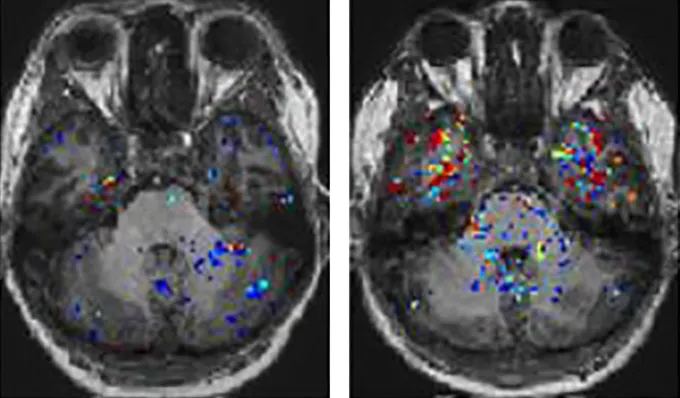

In patients with brain fog, MRI scans revealed signs of damaged blood vessels in their brains, researchers reported February 22 in Nature Neuroscience. In these people, dye injected into the bloodstream leaked into their brains and pooled in regions that play roles in language, memory, mood and vision.

An injected dye lit up all the participants’ brains during MRI brain scans. In people recovered from COVID, the dye had trouble crossing the blood brain barrier. Likewise, in long COVID patients without brain fog, the dye mostly stayed put, confined within blood vessels. But in eight of 11 participants with brain fog, the dye tended to escape from blood vessels and enter brain tissue.

“It was just so clear,” Campbell says. He remembers one of the first people scanned, someone with severe brain fog. Their temporal lobes, brain regions that sit behind the eyes, were “just flooded with this dye,” he says. The researchers’ work suggests that “brain fog wasn’t just a figment of [patients’] imagination,” Campbell says. “It was a very, very real thing that they were reporting.”